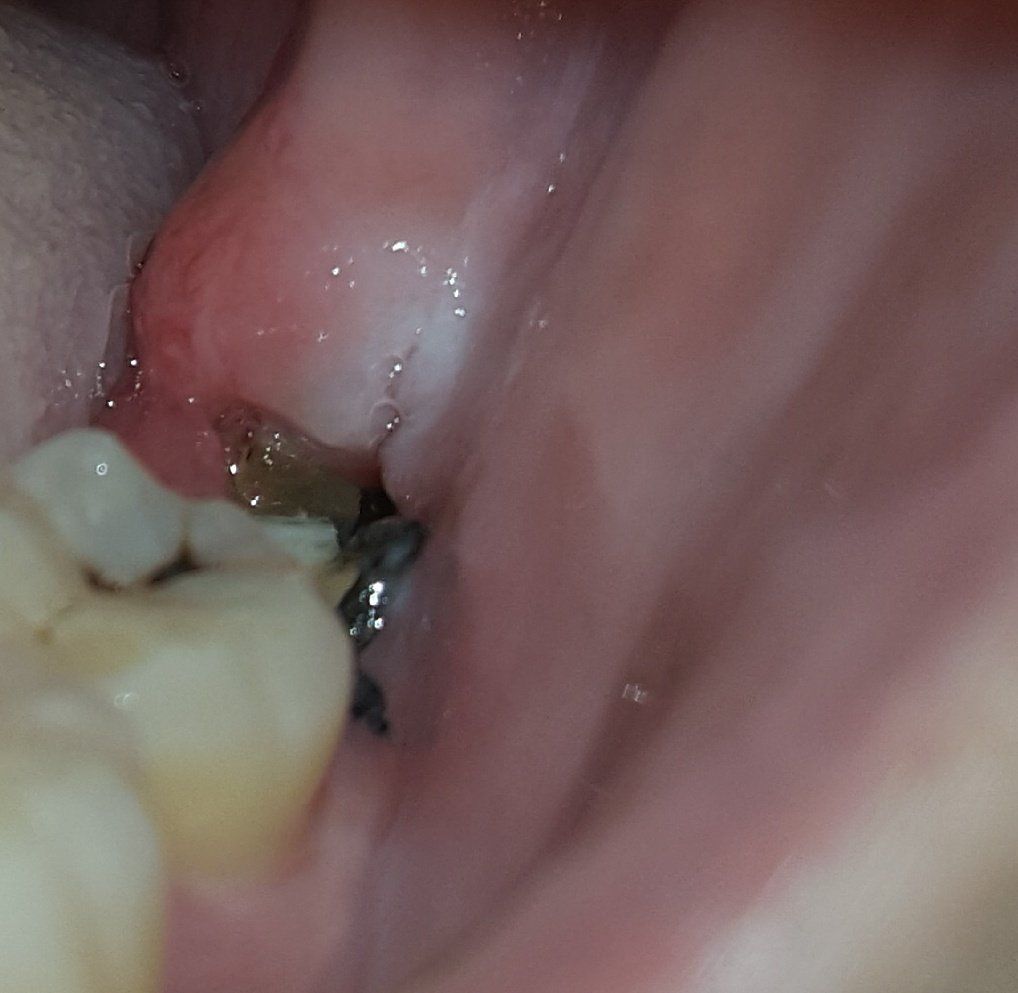

사랑니 발치 후 7일이 지났습니다. 사랑니 발치 후 혀 밑에 구내염이 나서 입도 크게 못벌리고 고생하다 구내염이 좀 나은 후 양치를 한 후 입을 크게 벌려 발치한 곳을 보니 구멍이 나 있는거 같아서 문의드립니다.. 조금 쎈 약을 먹어서 통증은 모르겠는데 발치 부위 부분 턱이 약간 뜨거워지고 있습니다..

사진 제대로 찍지 못한점 죄송합니다

• 1번 째 사진

현재 사진상 봉합사(실밥)가 보이는데, 발치 후 일주일이 지났다면 이를 제거하기 위해 치과에 내원해야 하므로, 내원하여 정확한 상태를 문의하시는 것이 좋습니다.

발치 한 이후에 일주일 정도 지났다면 현재와 같이 구멍이 나 있는 것은 당연합니다. 보통 잇몸으로 충분히 채워지기 위해서는 3~4개월 정도의 시간이 필요합니다. 또한 현재 실밥을 뽑더라도 해당 부위의 통증은 약간 존재할 수 있습니다. 정상적인 회복과정으로 보이나 통증이 점점 증가하거나 열감이 계속 지속된다면 이때는 치과 방문 후 검사를 해보는 것이 좋습니다.